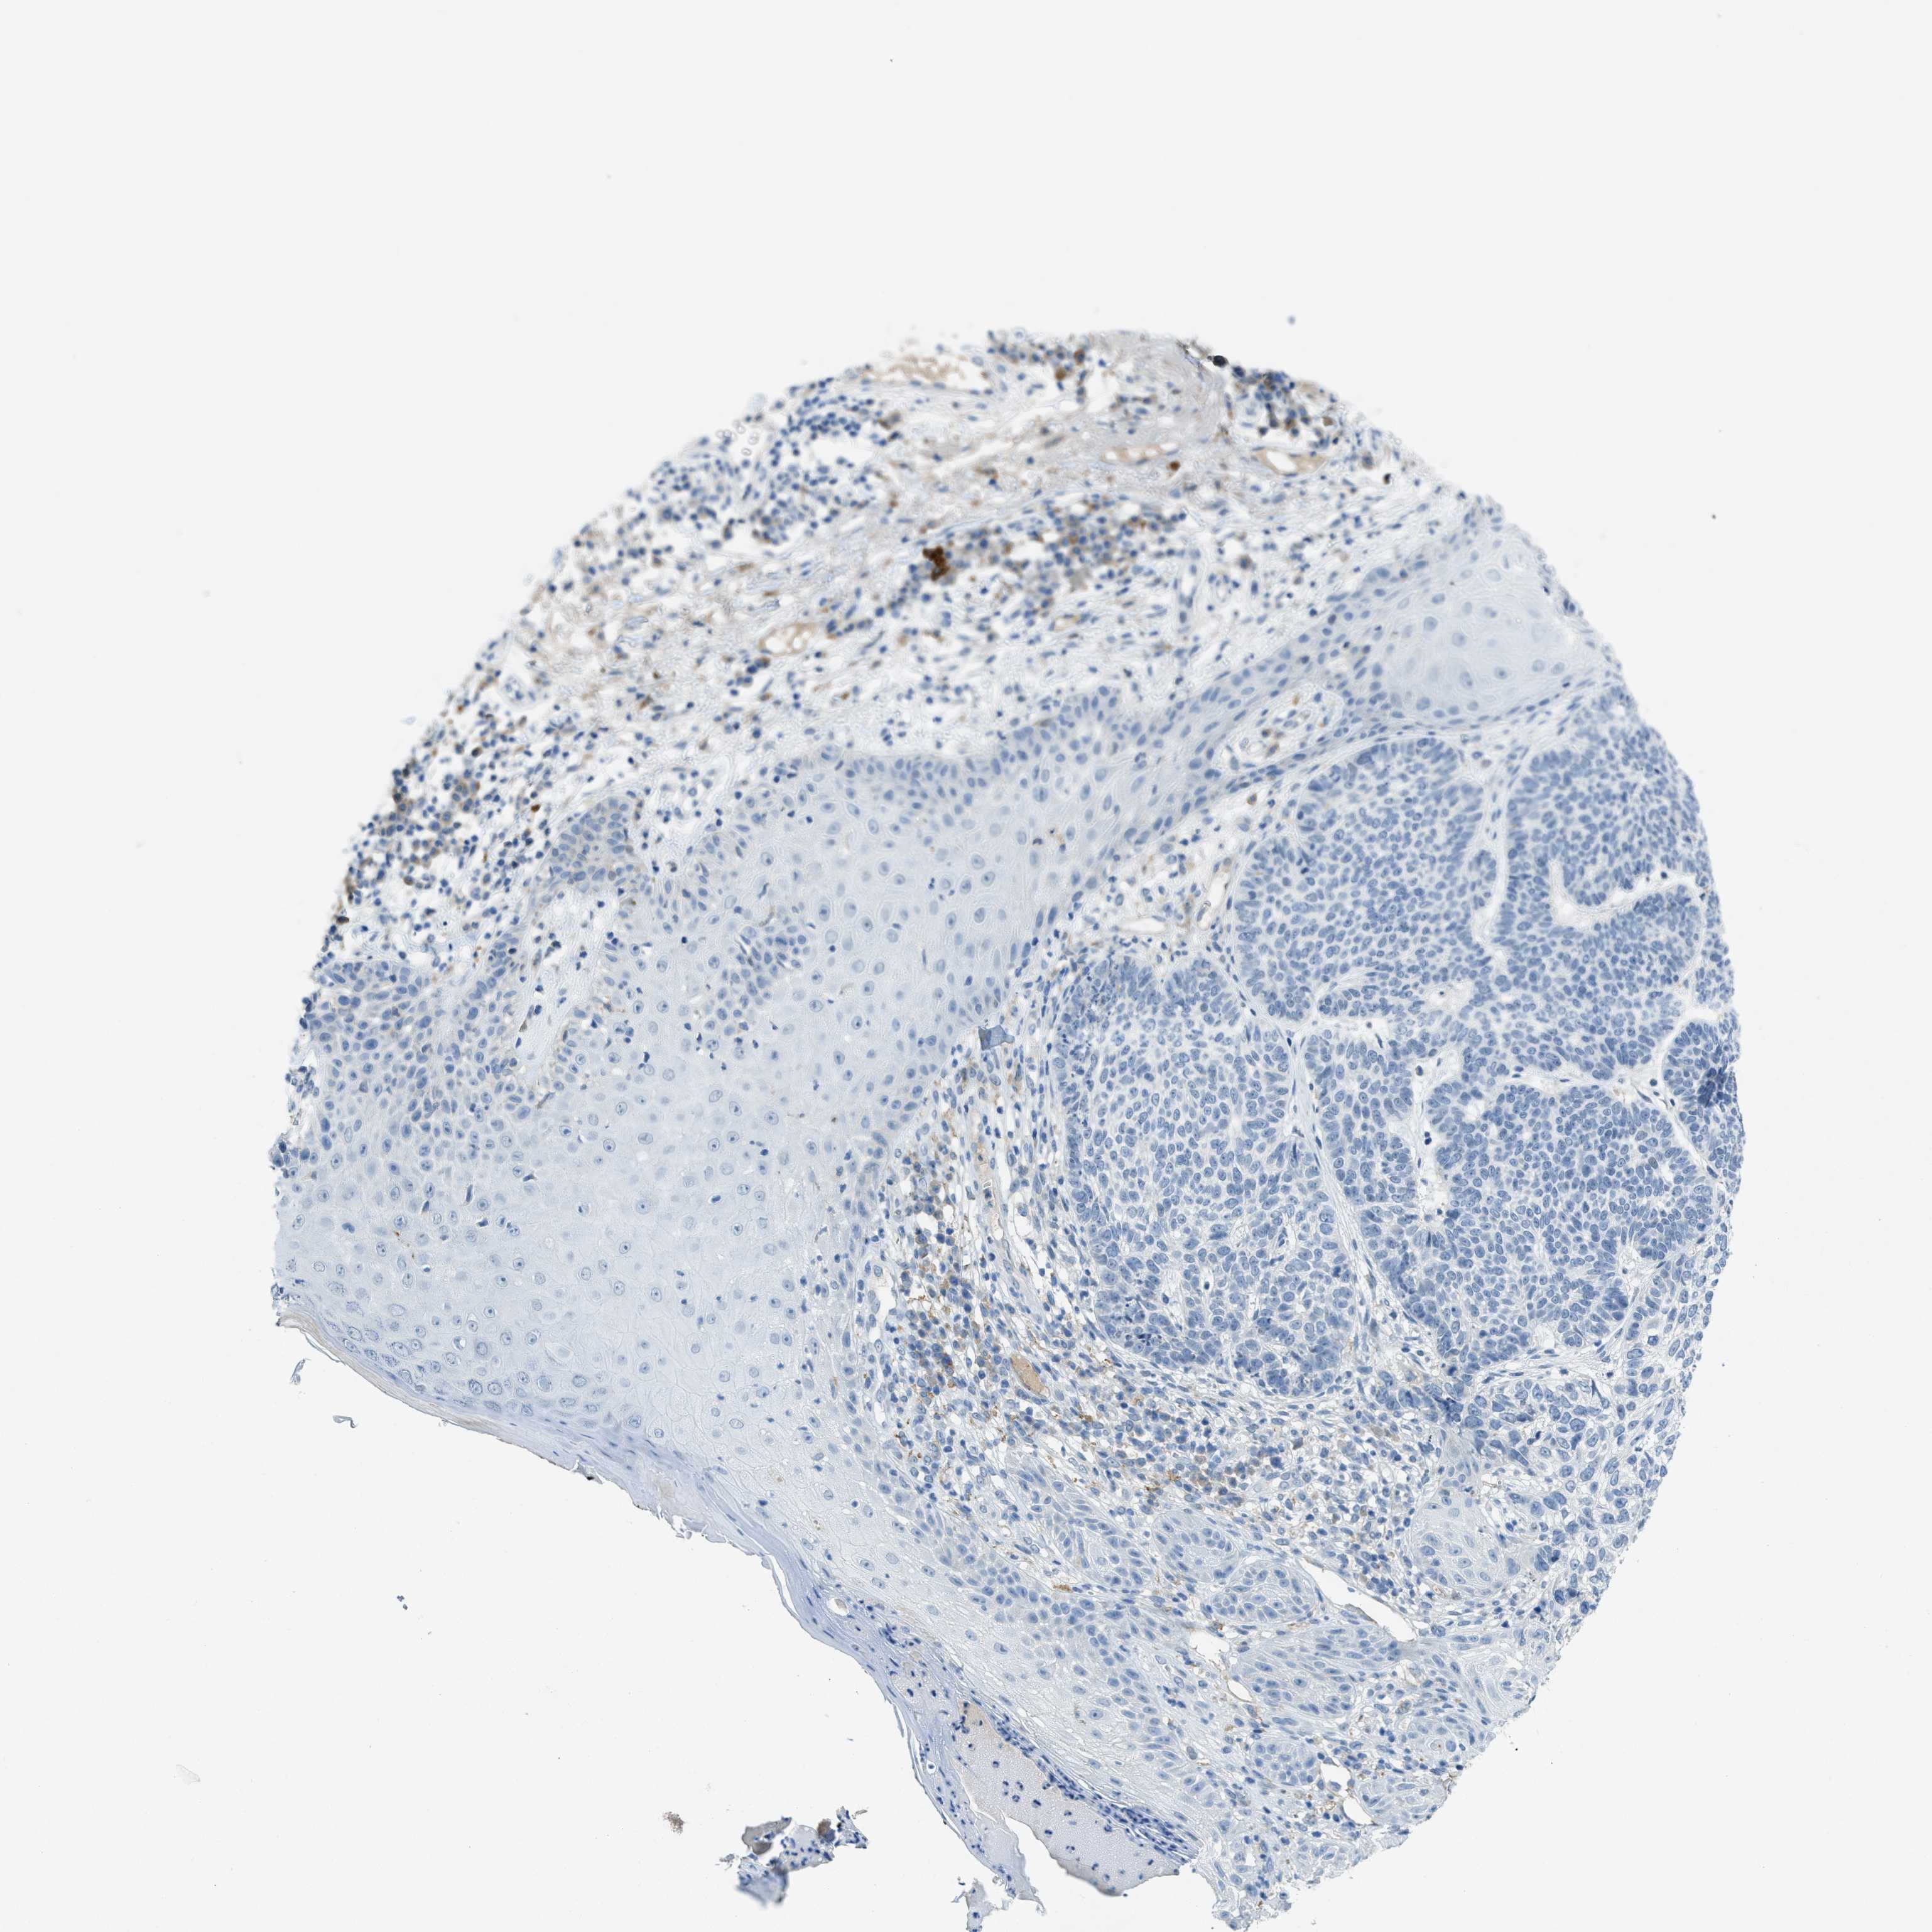

SKIN CANCER - Protein expressioni

A mouse-over function shows sample information and annotation data. Click on an image to view it in a full screen mode. Samples can be filtered based on level of antibody staining by selecting one or several of the following categories: high, medium, low and not detected. The assay and annotation is described here.

Each image is clickable and will lead to virtual microscopy that enables deeper exploration of all samples and also displays staining intensity scores, fraction scores and subcellular localization as well as patient and tissue information for each sample.

Antibody HPA013856

Antibody HPA017762

Squamous cell carcinoma, NOS

Basal cell carcinoma

Squamous cell carcinoma in situ, NOS

Squamous cell carcinoma, metastatic, NOS